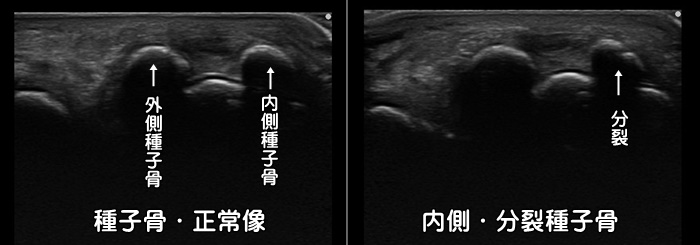

母趾種子骨障害・分裂種子骨

足の母趾の裏側(母趾球部)に痛みがあれば種子骨(しゅしこつ)と呼ばれる小さな骨に炎症が起こっているかもしれません。時に種子骨が割れて分裂しています。分裂していても症状のない方も沢山おられます。